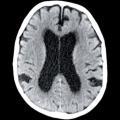

L’imagerie de référence est l’IRM cérébrale ; elle permet d’éliminer les diagnostics différentiels et d’obtenir une analyse morphologique et vélocimétrique.

Le signe le plus important est la ventriculomégalie objectivée par l’indice d’Evans (rapport entre le diamètre interne maximal des cornes frontales et le diamètre interne maximal du crâne, sur la même coupe axiale) [fig. 1].

Des sillons de la convexité médiane étroits, des dilatations focales des sillons de la convexité et un angle calleux aigu inférieur à 90 ° (fig. 1)5 constituent les autres signes radiologiques pertinents.

• L’IRM cérébrale montre une ventriculomégalie ainsi que d’autres signes de troubles de la circulation du liquide céphalo-rachidien.